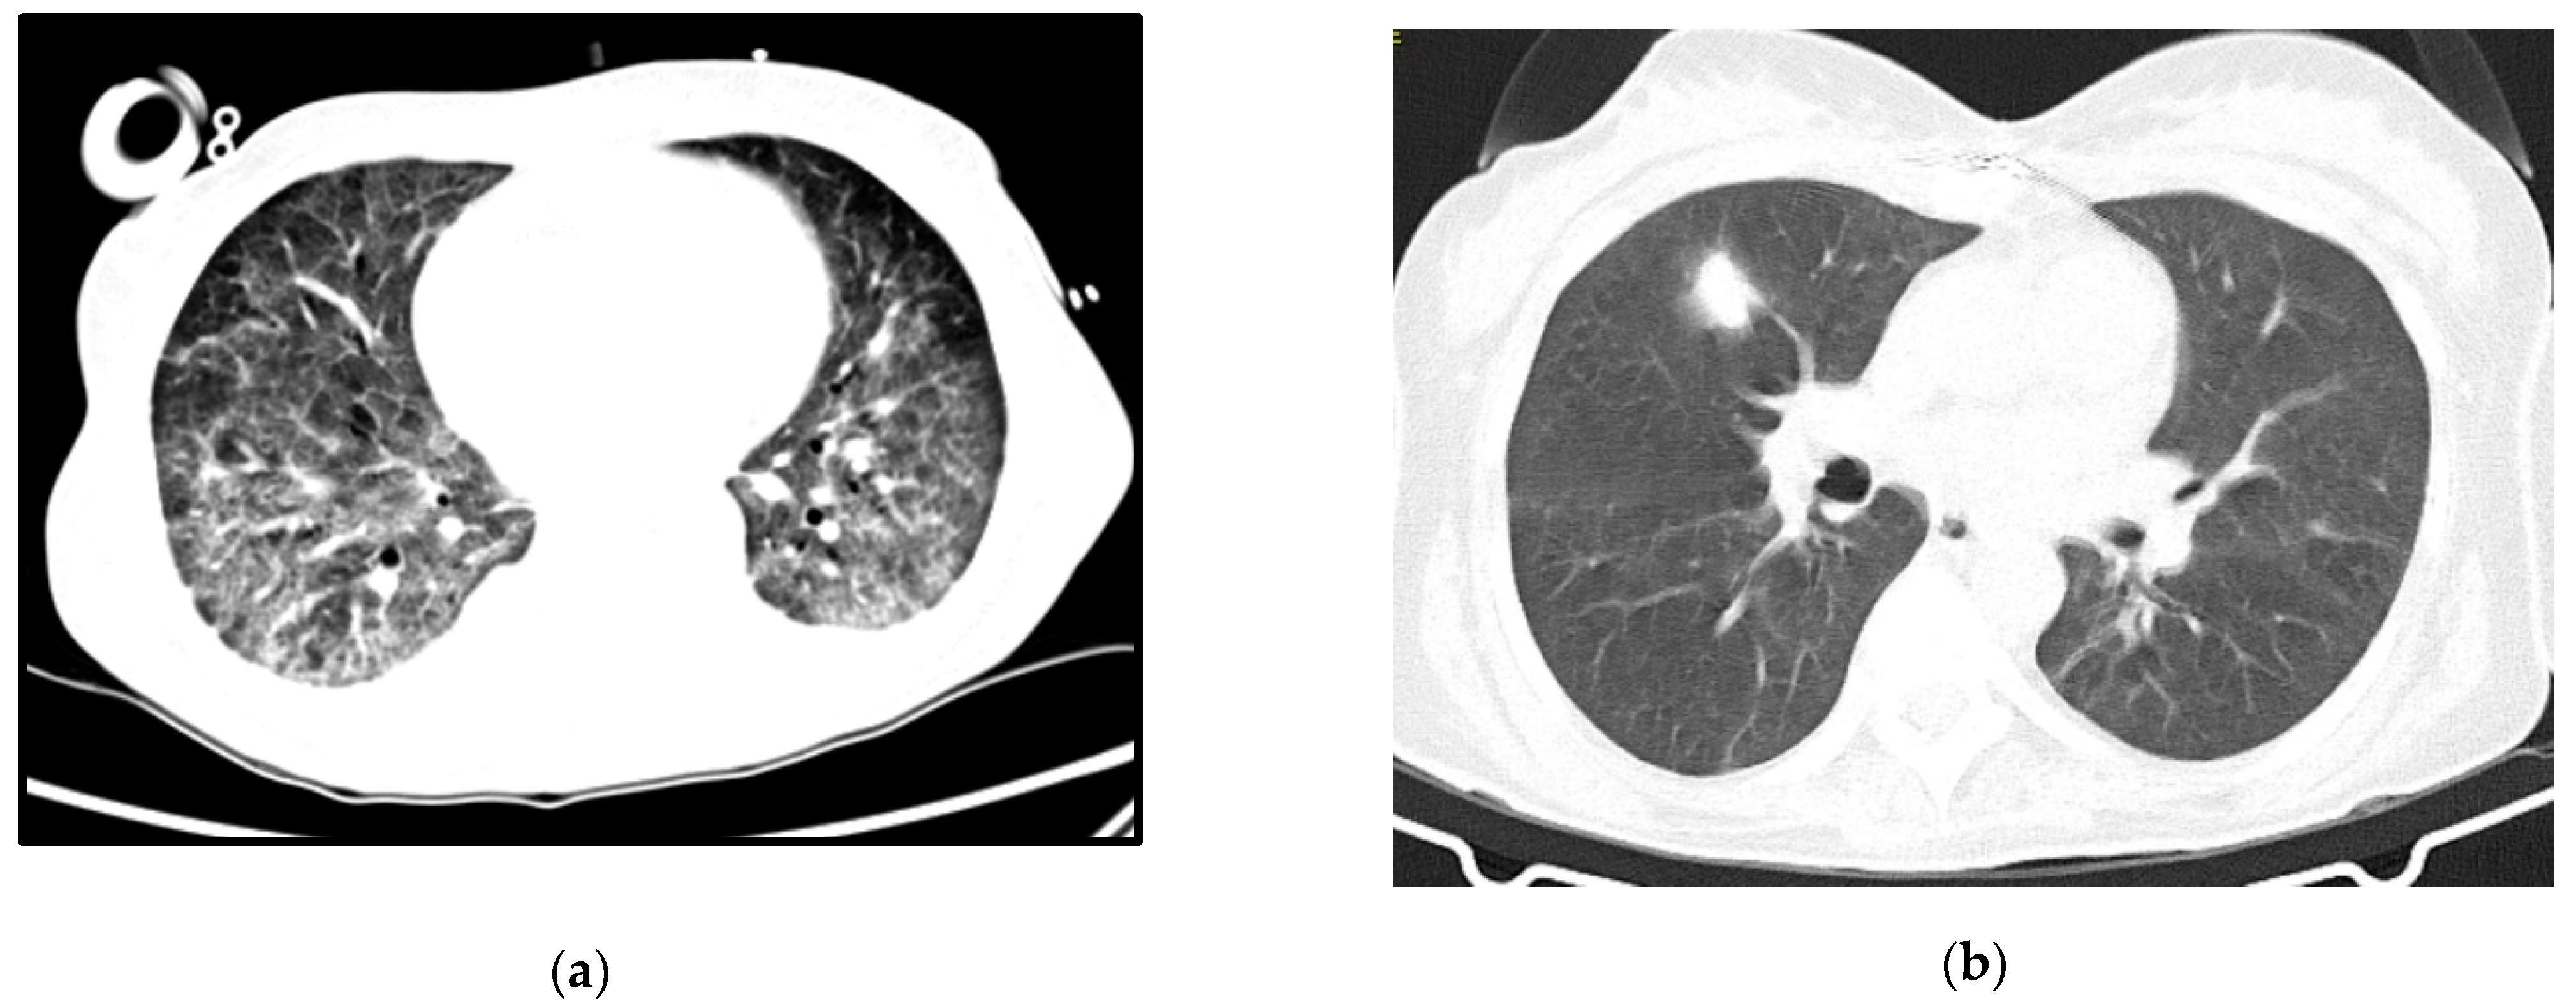

A 64-year-old woman with a history of hypertension, dyslipidemia and chronic pulmonary disease presented at the ER with fever, shortness of breath and a worsening cough despite a previous complete course of antibiotics for presumed CAP. She was hypoxic, with isolated elevation of CRP and diffuse ground-glass opacities on thoracic CT-scan (Figure 2a). Her status deteriorated despite antibiotics and oxygen supplementation in the Intermediate Care Unit, so she was transferred to the ICU and intubated. Three days after IMV and prone positioning, she was connected to VV-ECMO due to refractory respiratory acidemia. Anti-HIV testing was positive. Immune and viral study revealed severe immunosuppression (9 CD4+/mm3) and high serum viral load (4.050.000 copies/mL) and TMP-SMX plus corticosteroids were started for presumed PJP, at the recommended PJP treatment dosage. Diagnosis was confirmed by positive immunofluorescence for P. jirovecii in BAL.

Figure 2.

Case 2 thoracic CT-scan at diagnosis (a) and follow-up (b).

ECMO was discontinued after 10 days. During the weaning off invasive ventilation, there was recrudescence of ARDS with increased ventilatory parameters and need for prone positioning. Nosocomial infection was considered, broad spectrum antibiotics were started and bronchofibroscopy repeated, with persistently positive immunofluorescence for P. jirovecii and a positive polymerase chain reaction (PCR) for cytomegalovirus in BAL. She completed a total of 33 days of treatment with TMP-SMX and 21 days of ganciclovir with respiratory improvement and started ART. She was extubated after 83 days and was transferred to the ward after three months of ICU stay for muscular rehabilitation, without other dysfunctions.

Follow-up imaging can be seen in Figure 2b. She was transferred to a rehabilitation unit with a residual need of oxygen support (2 L per minute), from which she recovered after some months of pulmonary rehabilitation.